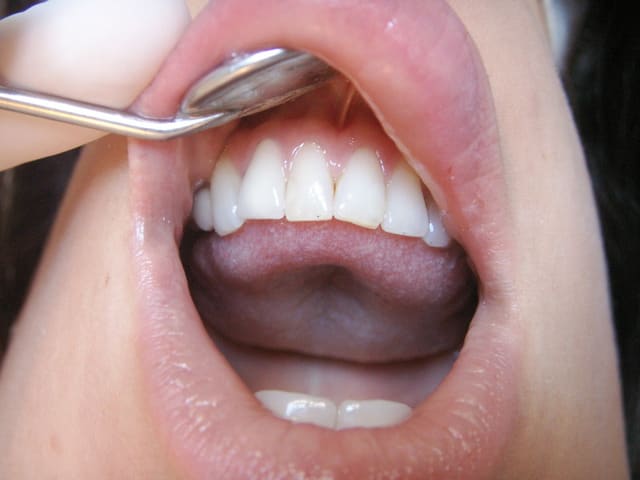

plus sérieusement mais suffisamment imparfait pour qu'on puisse trouver...

pour faciliter le chmilblick : sur une arcade il y a une seule prothèse visible et sur l'autre il n'y a qu'une seule dent naturelle visible

il s'agit d'un mix de facettes et couronnes céramo-céramiques

32 et 23

bravo Henri